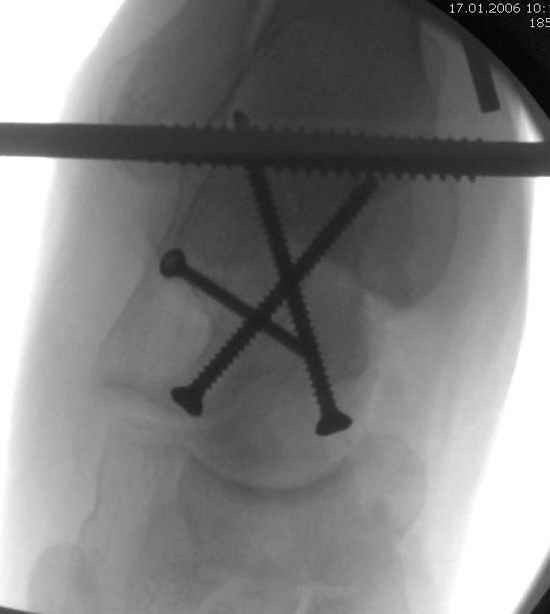

Вдогонку по поводу перелома таранной кости, больная 81, не страдает диабетом, перелом закрытый, в первый же день поступления ограничились временным наружным фиксатором (как на снимке).

Планировалась открытая фиксация после спадения отека, но больная пожелала лечиться по месту жительству в другом штате..

Из-за отека на стопе тактика лечения у всех была

одинаковая: временная наружная фиксация до спадения отека, при изолированных переломах они выписывались домой и через дней 7 госпитализировались на оперативное лечение.

Примеры на снимке...